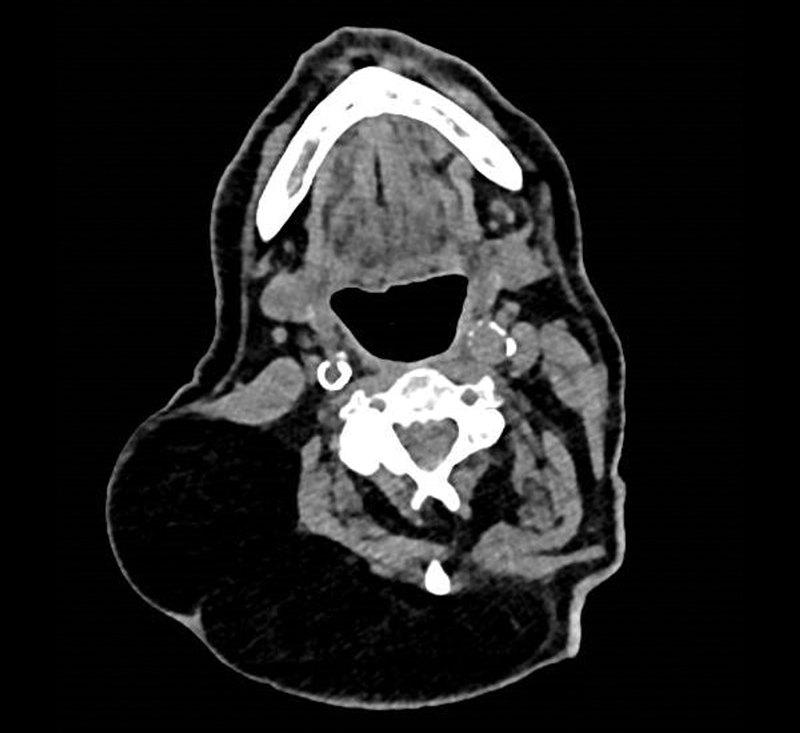

Un homme de 85 ans a une tuméfaction cervicale ancienne.

Quel est votre diagnostic ?

Sur le scanner, l'image hypodense est évocatrice d'une lipome.